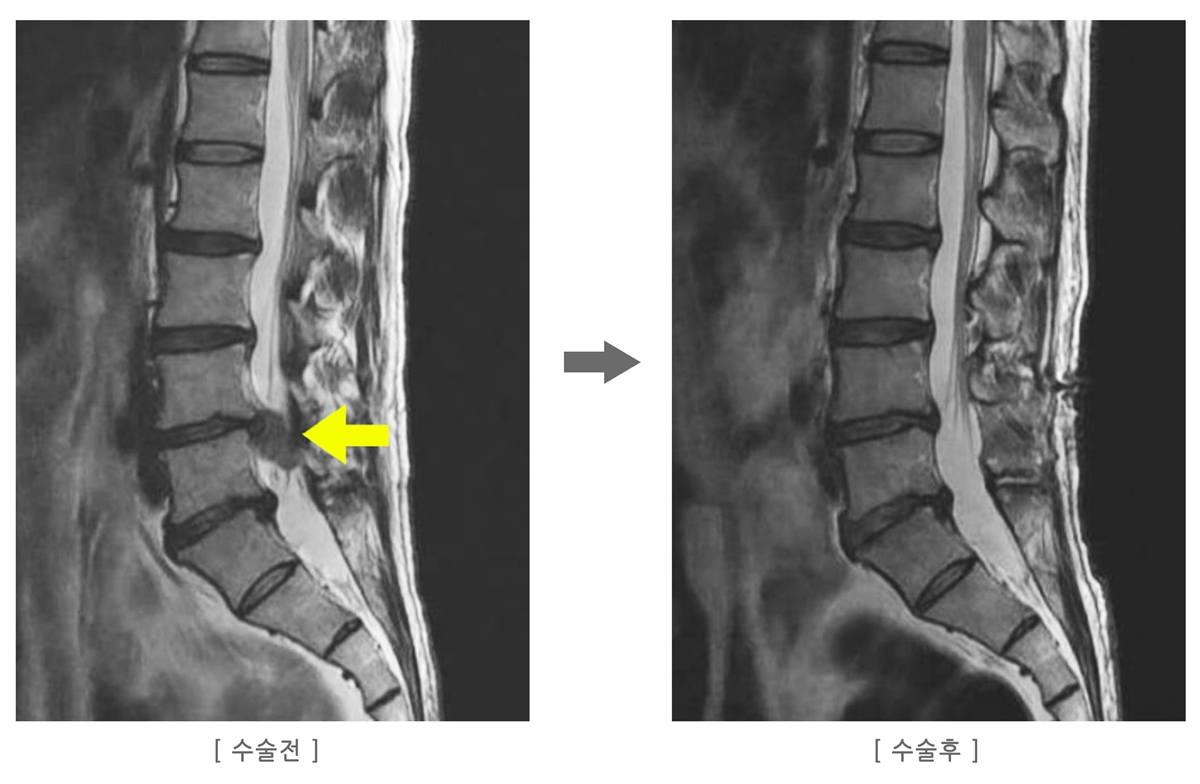

허리디스크 수술해야 할까? 기준은 명확합니다

허리디스크는 무조건 수술해야 하는 질환이 아니며, 전체 환자의 90%는 비수술로 회복됩니다.

하지만 아래 3가지에 해당하면 수술이 필요할 수 있습니다.

• 다리 힘이 빠지거나 저림이 심해 걷기 어려움

• 약물·주사·물리치료 6주 이상 해도 호전 없음

• 배뇨 장애 등 응급 신경 증상 발생